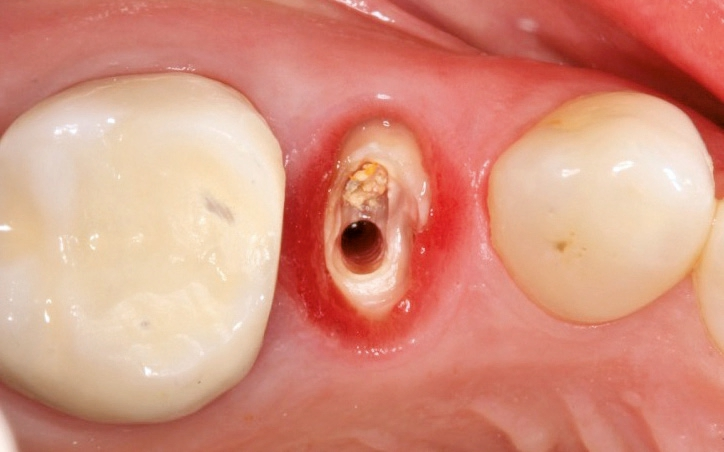

Atraumatische Extraktion

In einem ersten Schritt wurde eine knochenschonende Zahnentfernung unter Erhalt der bukkalen Knochenlamelle mit dem Easy X-Trac System (Benco Dental, Pittston, Pennsylvania, USA) durchgeführt. Für einen Gewindestift mit Abzugshilfe wurde dabei ein Bohrloch im entsprechenden Durchmesser und in senkrechtem Einschub gesetzt. Mit einer Handratsche wurde der Stift lagestabil in den erweiterten Wurzelkanal eingedreht. Ein Löffel mit einer Öffnung für den Stiftkopf wurde nun einprobiert und anschließend mit Knetsilikon so individualisiert, dass eine schaukelfreie Abstützung auf den Nachbarzähnen gewährleistet war. An dem aus dem Abformlöffel herausragenden Stiftkopf wurde nun das Extraktionsinstrument angebracht, das eine rein vertikale Kraft auf den Stift und damit auf die verbliebene Zahnwurzel überträgt. Dadurch kommt es zu einer kontrollierten Ruptur der Sharpey’schen Fasern. Ohne traumatischen Hebeleinsatz auf Gewebe und Knochen konnte der Wurzelrest so am Stück entfernt werden.